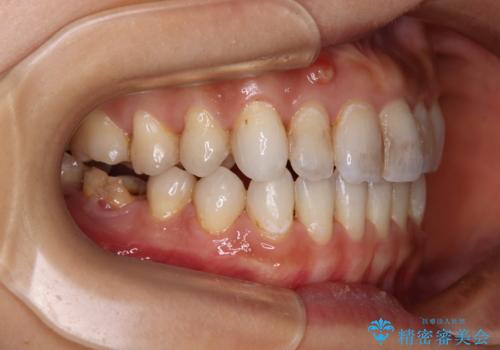

- 上下前歯の開咬とデコボコを気にして来院された患者様です。

開咬(オープンバイト)はインビザラインによる矯正治療がワイヤー装置と比べて圧倒的に有利であるため、インビザラインによる矯正治療を行うこととしました。

通院されなかった時期があって治療期間が長くなったり、奥歯に抜歯が必要な歯があったりと、治療は一筋縄にはいきませんでしたが、何とか治療を終えることができました。

今後はインプラント治療やむし歯治療を進めて行く予定です。